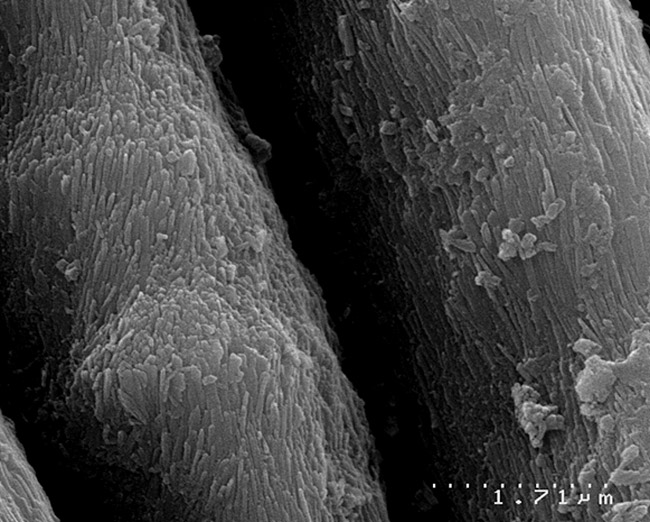

Recent evidence points to nanoparticle hydroxyapatite being the basic structural unit of enamel lost during occlusal wear, and it may play an important role in remineralization.13,14 The microscopic appearance on scanning electron microscope (SEM) images of unetched enamel compared to acid-etched enamel revealed that the mineral loss and gain in enamel could be in the form of nanoparticle crystallites (Figure 1 and Figure 2). The acid-etched enamel displays hydroxyapatite nanocrystals that are becoming separated from the structure.

As the acids penetrate deeper into the enamel, more minerals are lost from below the surface, the enamel becomes more porous, and there is a change in the enamel’s appearance because light diffracts differently between sound and porous enamel. At a microscopic level, the loss of interprismatic enamel exposes the enamel rods, and the nanoparticle infrastructure of the enamel becomes apparent (Figure 1).

SEM micrograph of normal enamel demonstrates the nanoparticle apatitic infrastructure (x60000 magnification).

Figure 1